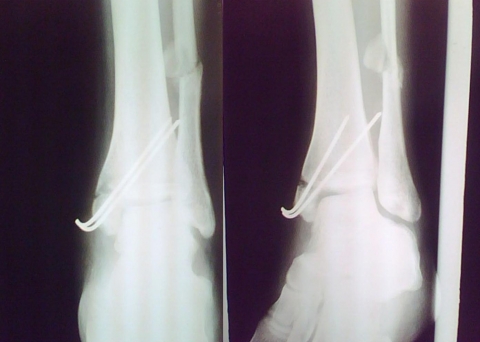

Paciente foi então submetido à nova cirurgia em nosso Serviço, tendo-se optado por fixação do maléolo medial pelo princípio de banda de tensão ( 2 FK e Fio de Cerclagem) com enxertia de tíbia proximal homolateral. Não realizada osteotomia da fíbula, então consolidada e algo encurtada.

Angulo talocrural pós-cirúrgico dentro dos padrões normais (8-15°), porém com 4mm de discrepância em relação ao lado contra-lateral.

Trata-se provavelmente de uma fratura tipo C de Weber e Supinação Rotação externa pela classificação Lauge-Hansenm que corresponde a aproximadamente 70% das fraturas do tornozelo do adulto. Não foi citado no caso a realização intra-operatória dos testes de estresse para sindesmose, de forma que, provavelmente, há lesão da sindesmose pelo traço de fratura. Minha conduta seria: 1) Iniciar síntese pela fíbula para ganho de comprimento e restabelecimento do angulo talo-crural; 2) Síntese do maléolo medial utilizando compressão inter-fragmentária com parafusos corticais de 3.5mm. Pelas imagens imagino que os fios K são de diâmetro 2.5mm e acredito que o risco de exposição dos fios (pelo trauma, repetidas abordagens e fio saliente na pele) é bastante elevado. Como disse, teria optado por síntese com parafusos.

Trata-se de uma fratura AO 44-C2,inicialmente deve ser tratada pelo principio da estabilidade absoluta, com osteossintese do maleolo medial e lateral, utilizando 02 parafusos de esponjosa 3,5 mm no medial e placa 1/3 tubular na fibula;Se temos principios, escolhemos nossos proprios metodos; com 50 dias de fratura,estamos tratando uma complicaçao de fratura,o tirante de tensão é uma opção no maleolo medial e a fibula não devem ter fixado pois devia está consolidada